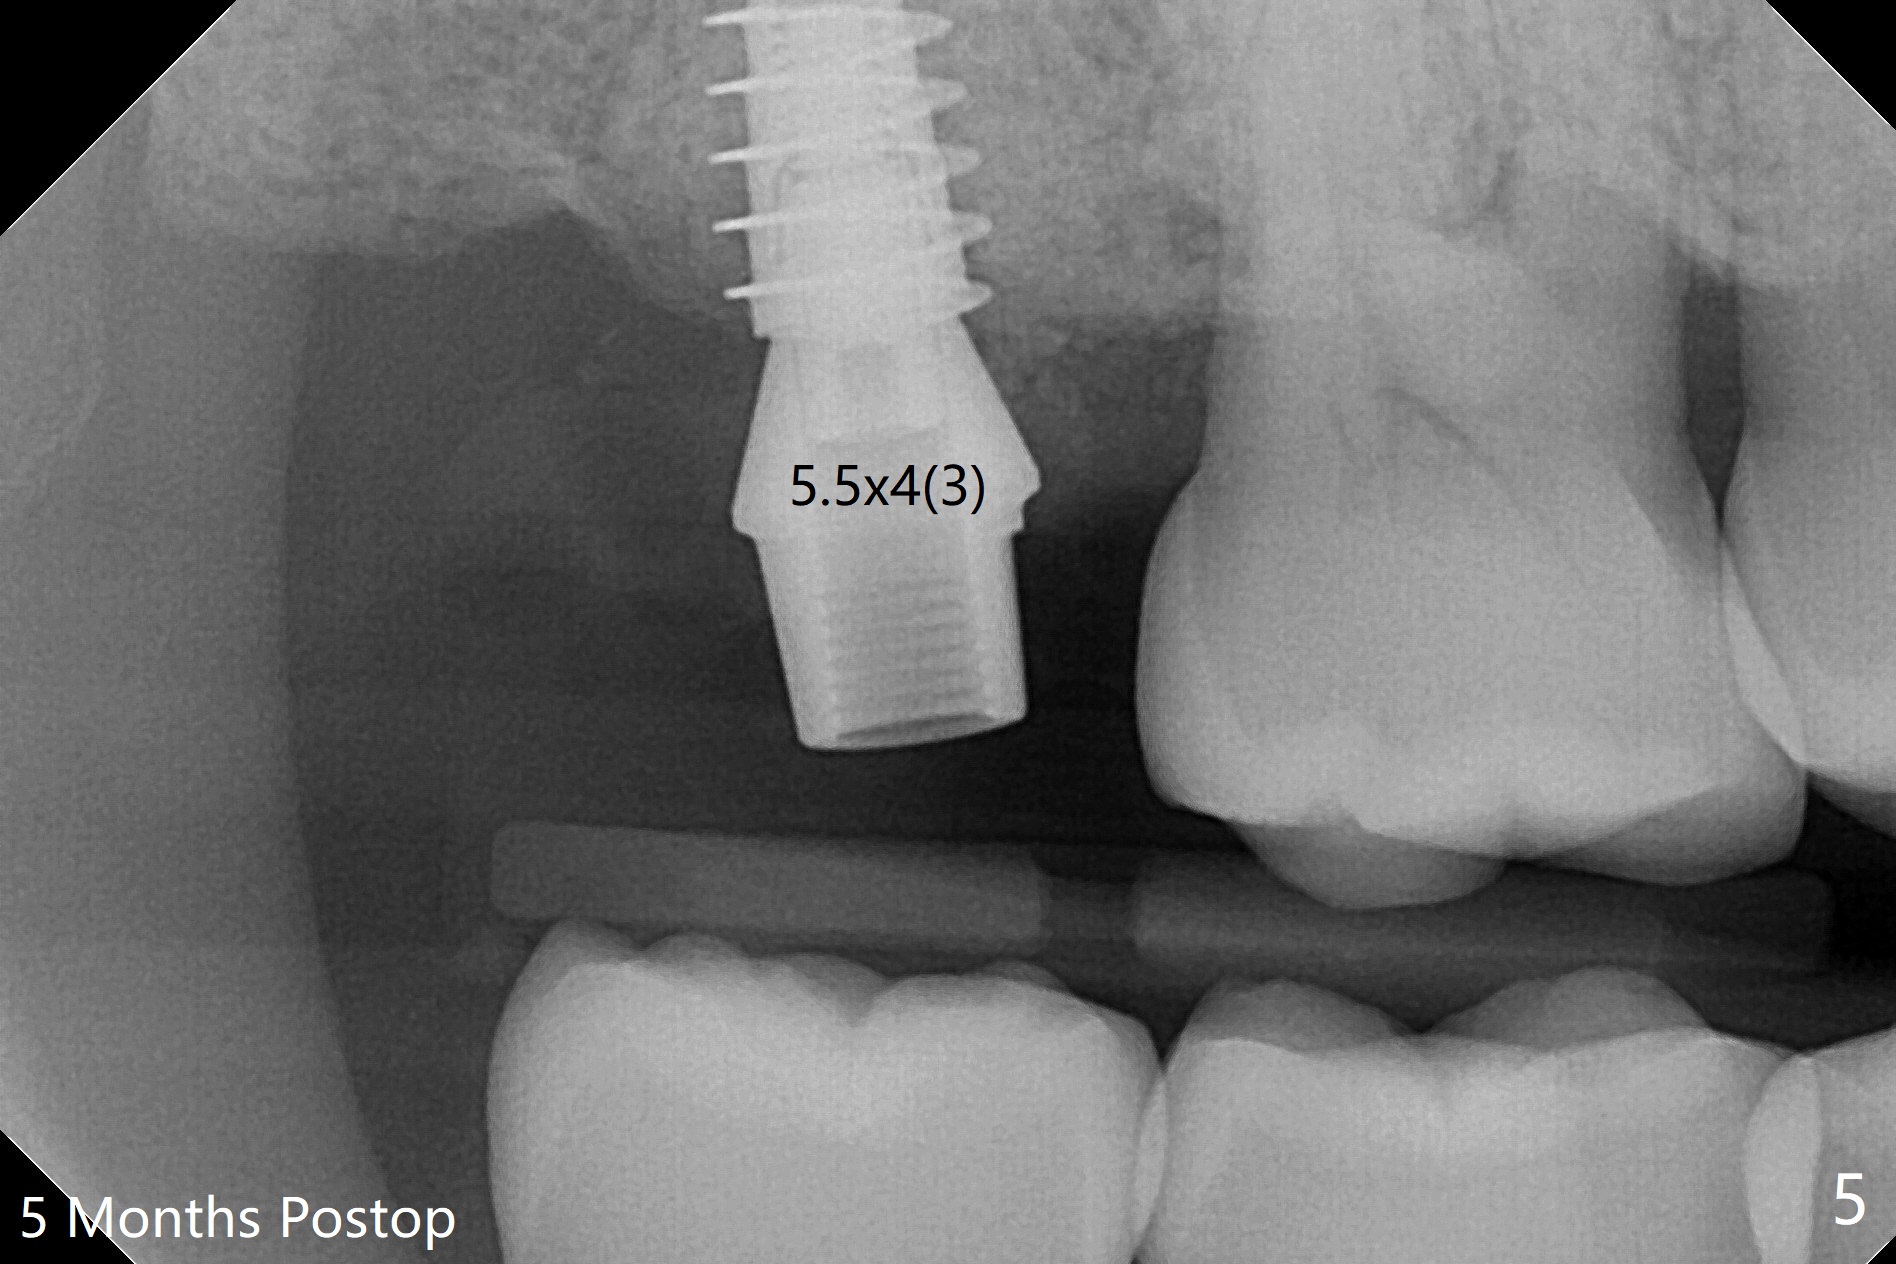

术前CT显示右上7牙槽骨不平,可能造成植体偏移,腭侧,远中螺纹暴露,为了方便导板种植后植骨,切开翻瓣,牙槽骨外形与CT检查一致,不过1.5毫米offset牙槽嵴磨平钻头所形成钻洞正常,除了骨质密度高之外,术中临床和射线检查发现植体方向和种植水平与设计一致,没有偏移(图一至三),最后只有腭侧一个螺纹暴露,放置愈合基台后,放入粘性骨粉,覆盖PRF膜,近中,远中各缝合一针,其余使用牙周胶水关闭伤口。不偏位可能原因:使用1.5毫米offset,骨质密度高,两侧密度接近。术后一周远中伤口裂开(图四:*),近中,远中应该多缝合一针。术后三周伤口愈合。The implant threads are subcrestal 5 months postop (Fig.5).